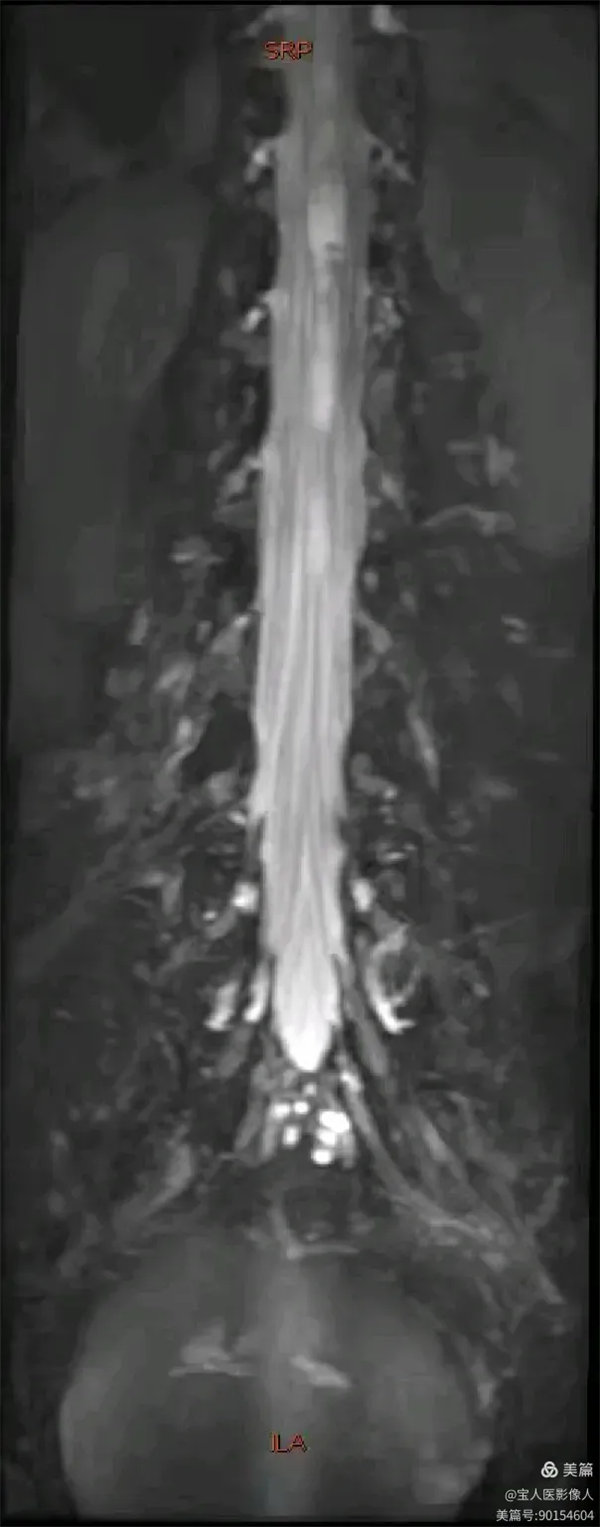

最大密度正面圖,顯示腰段硬膜囊內腦脊液(高信號),多條終絲(線狀稍低信號)縱向走行清晰。

最大密度正面圖,顯示腰段硬膜囊內腦脊液(高信號),多條終絲、腰神經及骶神經(線狀稍低信號)走行清晰。